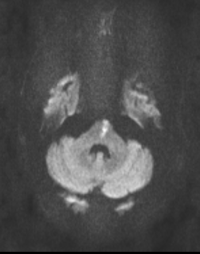

Series 001 — Frontal Lobe Mass (Likely Meningioma) Overview

Initial scan set with key anatomical landmarks and first-pass observations.